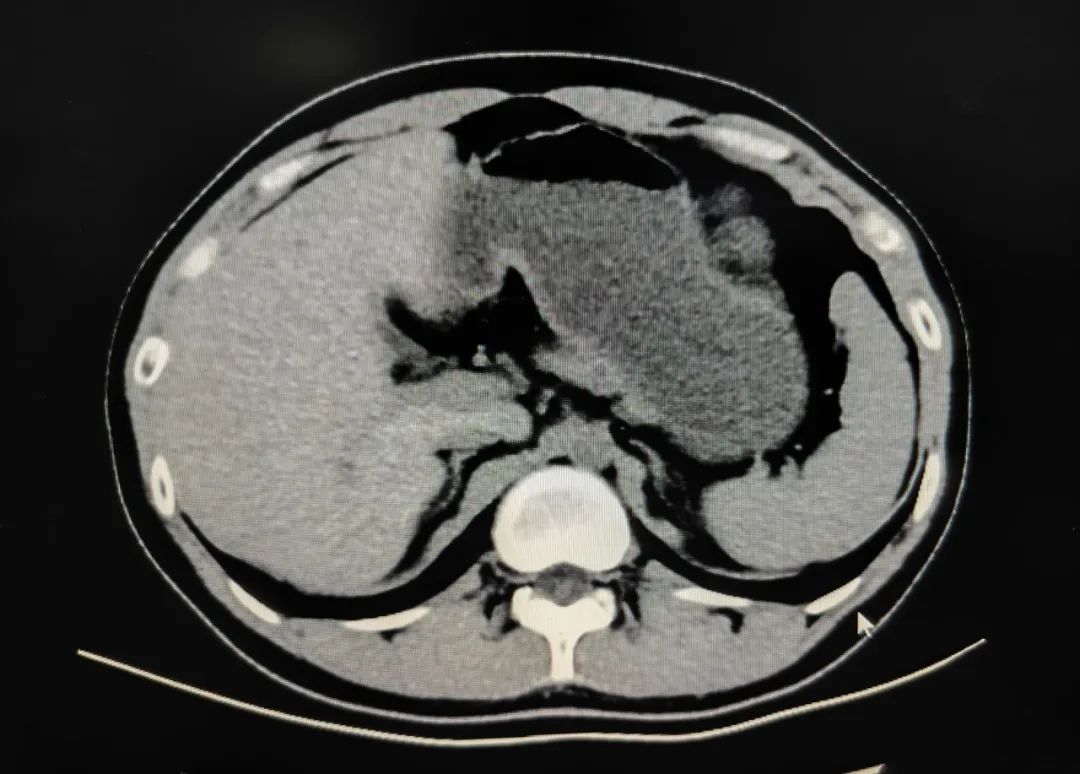

再来看一张没有禁食的,各类食物与水相比密度不均,容易与病变混淆。建议4小时以上空腹且多喝水。